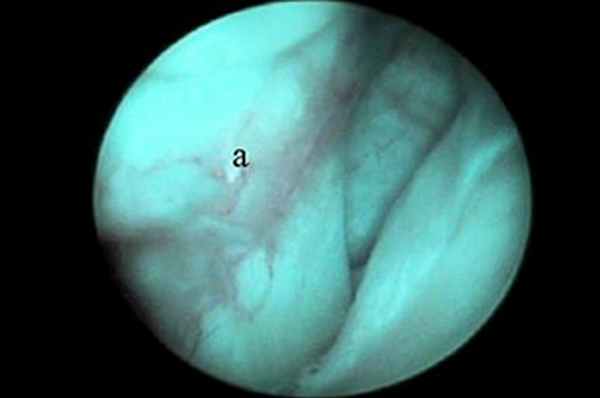

Артроскопия плечевого сустава

Показания к артроскопии плечевого сустава включают РОХ головки бедренной кости, нестабильность сустава, тендосиновит сухожилия двуглавой мышцы плеча, повреждение сухожилия подлопаточной мышцы и переломы хряща. Благодаря артроскопии плечевого сустава стало возможно диагностировать и лечить причины хромоты, сложно поддававшиеся диагностике ранее. Сухожилие двуглавой мышцы (рис. 1), Y-образная медиальная суставно-плечевая связка (МСПС) (рис. 2) и каудальная часть головки плечевой кости хорошо визуализируются.

| Рис. 1. Место прикрепления сухожилия двуглавой мышцы на надсуставном бугорке хорошо визуализируется с помощью артроскопа. Артроскоп можно продвинуть ниже через межбугорковую борозду для оценки состояния сухожилия по его ходу вдоль борозды. Рис. 2. Медиальная суставно-плечевая связка (МСПС) хорошо визуализируется с помощью артроскопа (а). Рис. 3. Каудальная часть головки плечевой кости (а) и суставная впадина лопатки (b). | ||